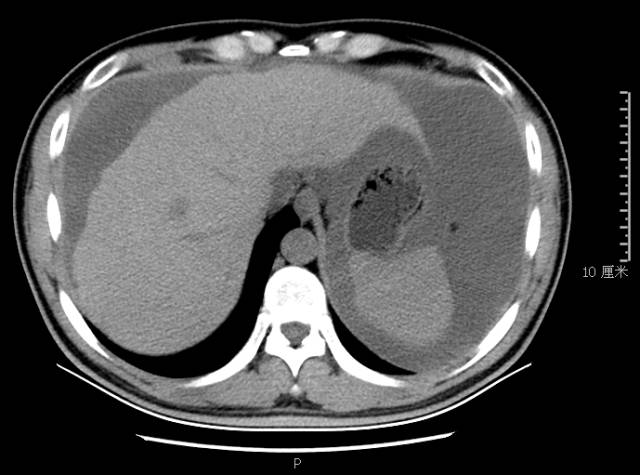

ct表现肝是腹部外伤时易累及的实性器官,仅次于脾,肝创伤的原因包括